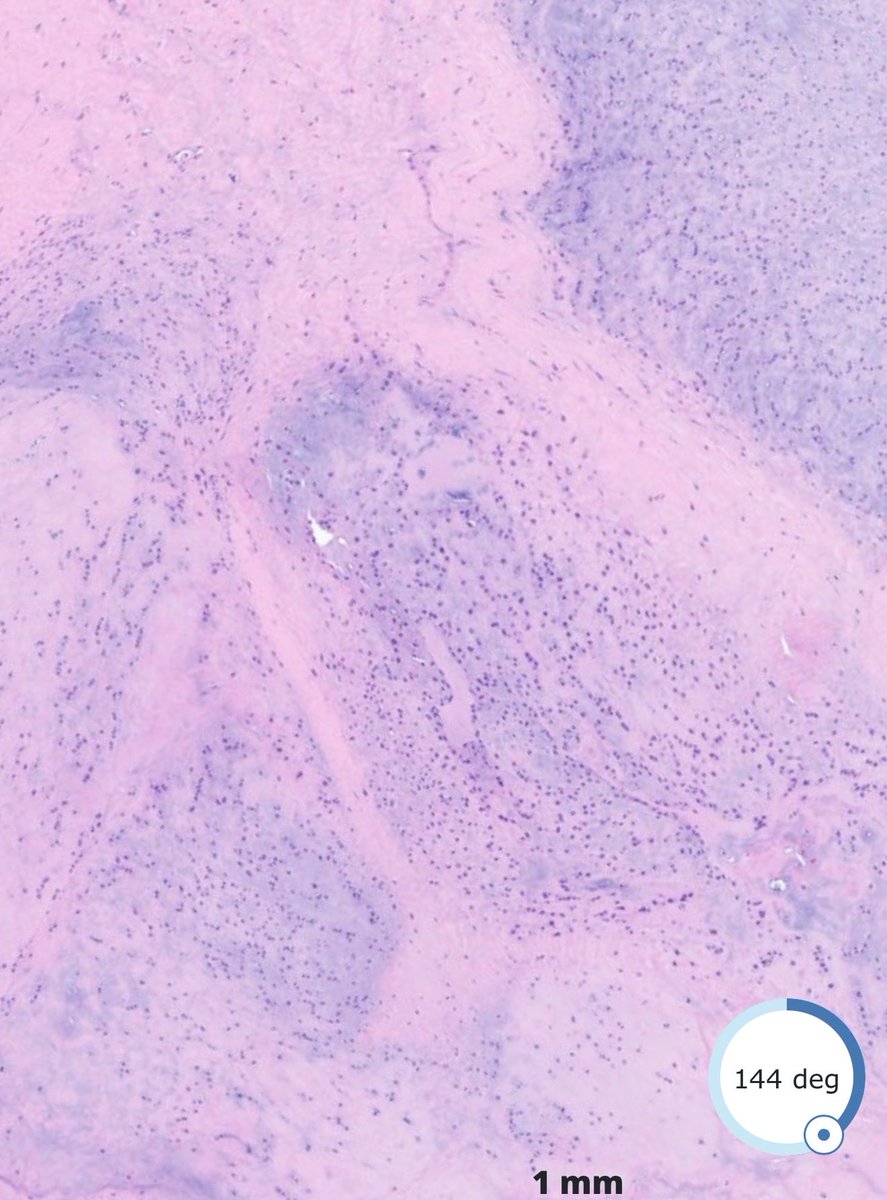

61F never smoker, large axillary mass with widespread Mets including multiple brain Mets. CD10 strongly positive (shown). Mutations in p53, RB1, and TERT. DDx? Stain suggestions? #pathx #pathtwitter #cnspath #neuropath #neuropathology

PeterKobalka's tweet image. 61F never smoker, large axillary mass with widespread Mets including multiple brain Mets.   CD10 strongly positive (shown). Mutations in p53, RB1, and TERT.  DDx?  Stain suggestions?  #pathx #pathtwitter #cnspath #neuropath #neuropathology